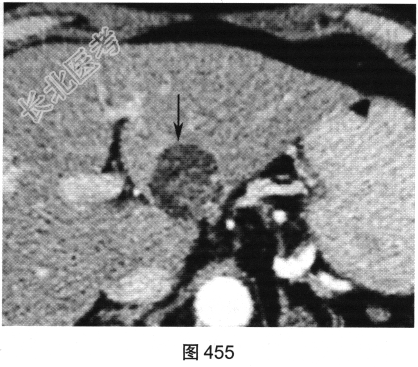

- [材料题] 患者女性,63岁,长久上腹痛并恶心、呕吐、寒战入院。超声提示肝脏有一高回声、边界清的肿块。患者进一步行肝脏CT检查,如图454~图456所示。

- 多项选择题3.对肝血管平滑肌脂肪瘤描述不正确的是( )

A、可与肾脏血管平滑肌脂肪瘤、多发结节性硬化并存

B、临床上患者可有上腹部不适、呕吐或疼痛等症状

C、均为良性肿瘤

D、由数量不等的平滑肌细胞、脂肪和增生血管组成

E、间叶源性肿瘤

F、多发生于成年女性

- 多项选择题4.该患者下一步需如何处理( )

A、无需处理

B、定期复查

C、外科手术切除

D、化疗栓塞

E、放射治疗

F、射频消融